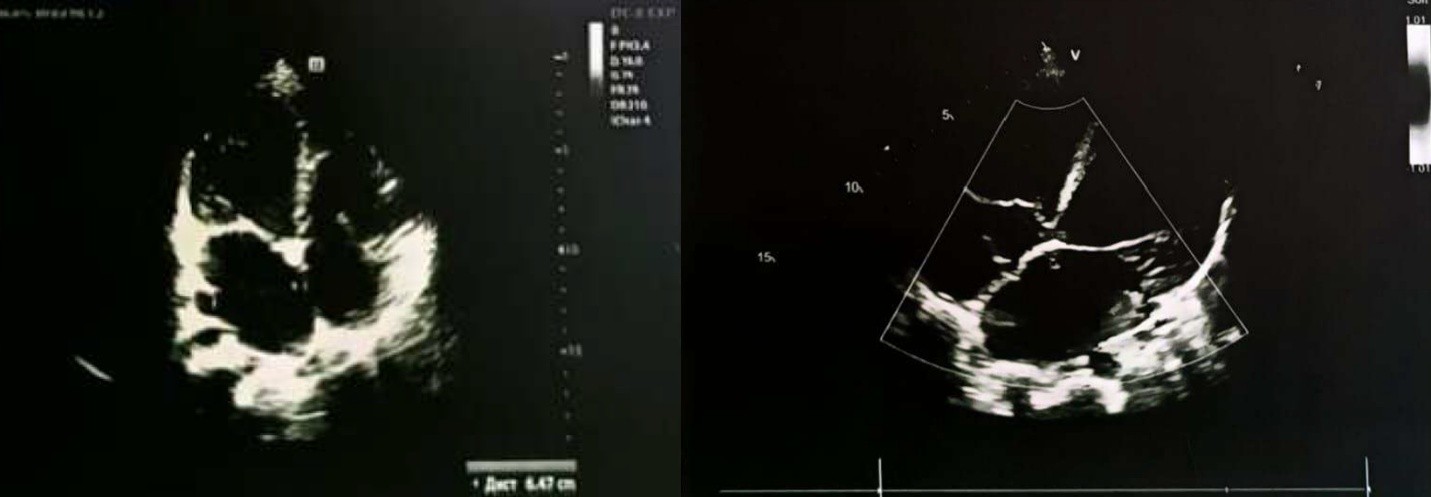

Пациентка ранее считалась практически здоровой, активно занималась танцами с 5-летнего возраста, хорошо переносила высокие физические нагрузки. В январе и феврале 2025 года дважды перенесла ОРВИ. Несмотря на симптомы (кашель, гипертермия до 38,5°С), она продолжала ежедневные интенсивные физические нагрузки (занятия танцами). В терапии применялись осельтамивир, бромгексин и тимьяна ползучего травы экстракт + калия бромид. В начале марта 2025 года после танцев состояние резко ухудшилось: появились боли в груди, выраженная слабость и одышка при минимальной нагрузке (подъем на 1 этаж). Обратились в поликлинику к участковому педиатру. Как отметила мать, ранее ЭхоКГ не проводилось, а у кардиолога они не наблюдались. При первичном обследовании по результатам ЭхоКГ были выявлены признаки критического снижения сократительной способности миокарда, диастолическая функция левого желудочка была снижена, фракция выброса составила 17% (рис. 4). Отмечалась выраженная дилатация левого желудочка и предсердия, а также умеренная дилатация правого предсердия и желудочка (рис. 1) В тот же день, после обращения в поликлинику и выявления критических изменений на ЭхоКГ, пациентка была экстренно госпитализирована в ГБУЗ СК «КДКБ» г. Ставрополь. На амбулаторном этапе терапия, направленная на лечение сердечной недостаточности, не проводилась.

Рисунок 1 - Эхокардиографическое исследование Пациентки на догоспитальном этапе: визуализация выраженной дилатации полостей сердца

При эхокардиографическом исследовании перикард без особенностей; перикардиальная жидкость в физиологическом объёме, сепарация листков перикарда до 2,0 мм. Отмечается выраженная дилатация полости левого желудочка и левого предсердия, умеренная дилатация правых отделов сердца. Фракция выброса ЛЖ по Teicholz составила 36% (норма — более 60%), по методу Simpson — 24% (норма — более 55%) (рис. 4). Выраженное снижение глобальной сократительной способности миокарда левого желудочка. Выявлен вторичный дефект межпредсердной перегородки диаметром 7,0 мм с перекрестным шунтом. Митральная регургитация III степени; трикуспидальная регургитация — умеренная. Отмечается повышенная трабекулярность стенок ЛЖ и диффузные изменения миокарда левого желудочка и межжелудочковой перегородки. Незначительная лёгочная гипертензия (рСДЛА — 37,0 мм/Hg).